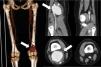

Se realiza ecografía (fig. 1) y angio-TAC (fig. 2), diagnosticándose como aneurisma poplíteo gigante. Ecocardiograma y estudio oftalmológico normales. Se interviene de forma preferente (fig. 3), con colocación de injerto de vena safena invertida.